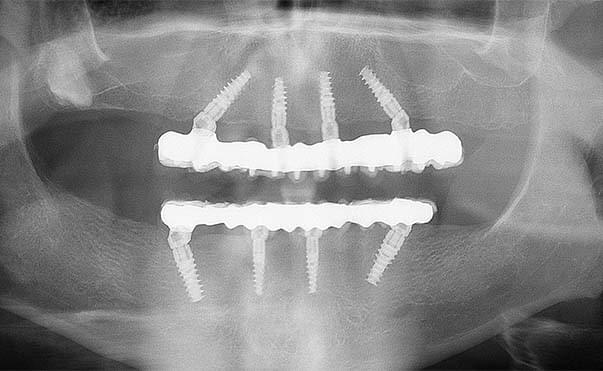

All on four Implant Treatment